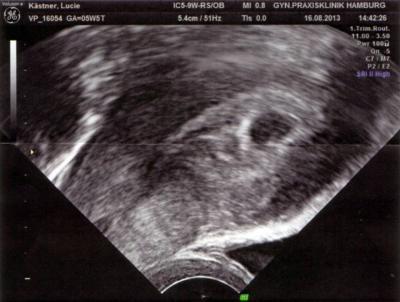

Alles zeitgemäß entwickelt, eine fruchthöhle mit Inhalt. Foto hängt dran, ist nur nicht so gut zu sehen. Nächster Termin ist am 30.8. :-) Bin im 7. Himmel. 5+4 bestätigt.